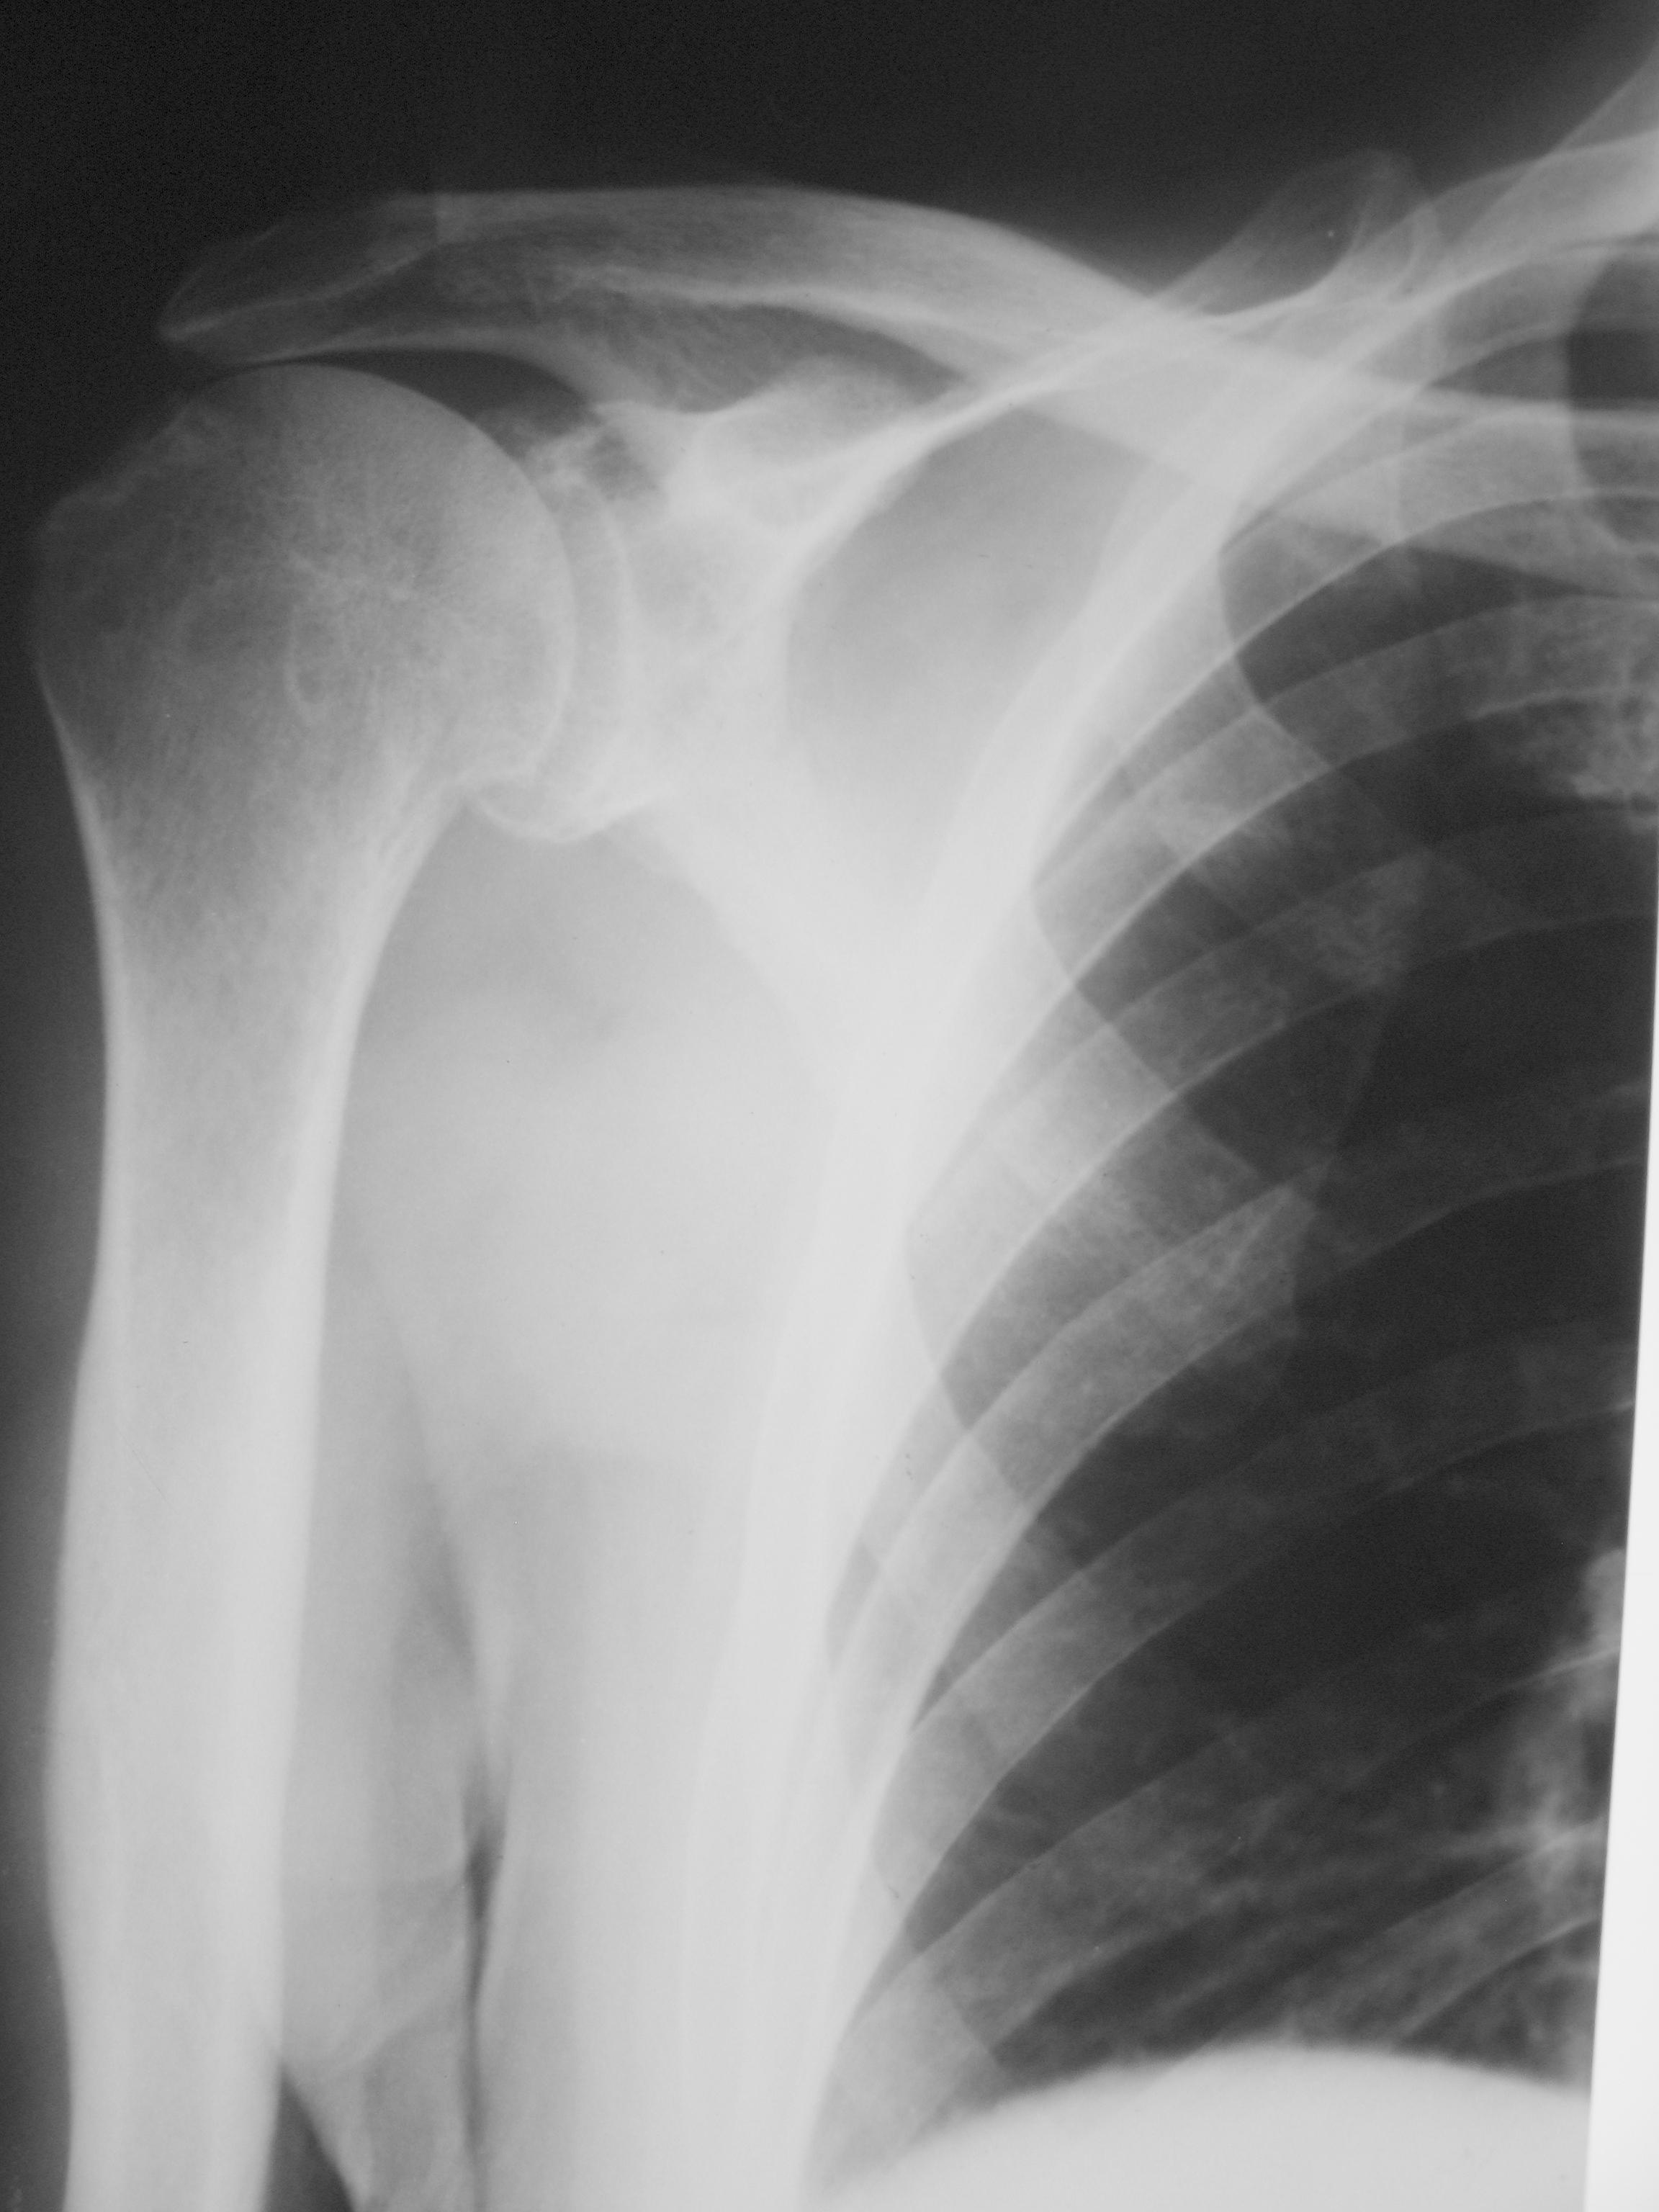

Рентгеновские снимки саркомы плечевого сустава